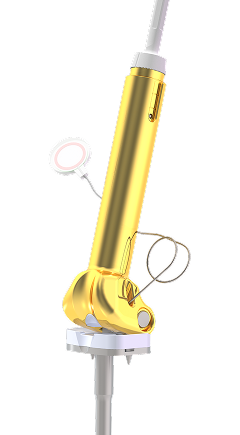

Le système Xpand est un système de croissance prothétique permettant l’allongement non invasif de prothèses massives dans les cas de reconstruction tumorale chez les jeunes enfants et adolescents n’ayant pas terminé leur croissance au moment de la résection tumorale.

La prothèse massive est équipé d’un micro – moteur entraînant l’allongement de la diaphyse prothétique. La technologie repose sur le transfert d’énergie. Un générateur haute fréquence dans l’unité de contrôle (émetteur) transmet l’énergie requise via un récepteur placé en sous cutané.